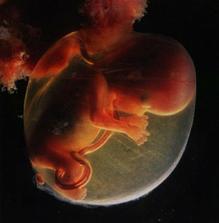

Jak asi víte, těhotenství je členěné na tři časové úseky, kterým říkáme trimestry – každý z nich trvá tři měsíce. Každý z trimestrů je zcela specifický, probíhají v něm určité charakteristické změny, podstupuje se vyšetření a nesou s sebou jiné pocity a obavy nastávající maminky.

Lékaři počítají týdny těhotenství od prvního dne poslední menstruace před otěhotněním. V prvních dvou týdnech tehotenství tedy žena těhotná není, protože k oplodnění vajíčka dochází až zhruba 14 až 21 dní od začátku menstruace.

1.-2. týden těhotenství

Vajíčko ve vejcovodu čeká zhruba 12 až 24 hodin na příchod spermií. V ejakulátu je v průměru 250 milionů spermií, z toho pouze zhruba 400 se dostane až k vajíčku ve vejcovodu, přičemž cesta z pochvy do vejcovodu trvá spermiím až 10 hodin. Obvykle pouze jedna spermie uspěje a pronikne po zhruba 20 minutách snahy do vajíčka. Tím dojde ke vzniku oplodněného vajíčka, tzv. zygoty. V příštích 10 až 30 hodinách dochází ke splynutí genetických informací vajíčka a spermie. Pohlaví dítěte je určeno již v této chvíli – pokud spermie nese chromozom Y, narodí se chlapec, pokud chromozom X, narodí se dívka.